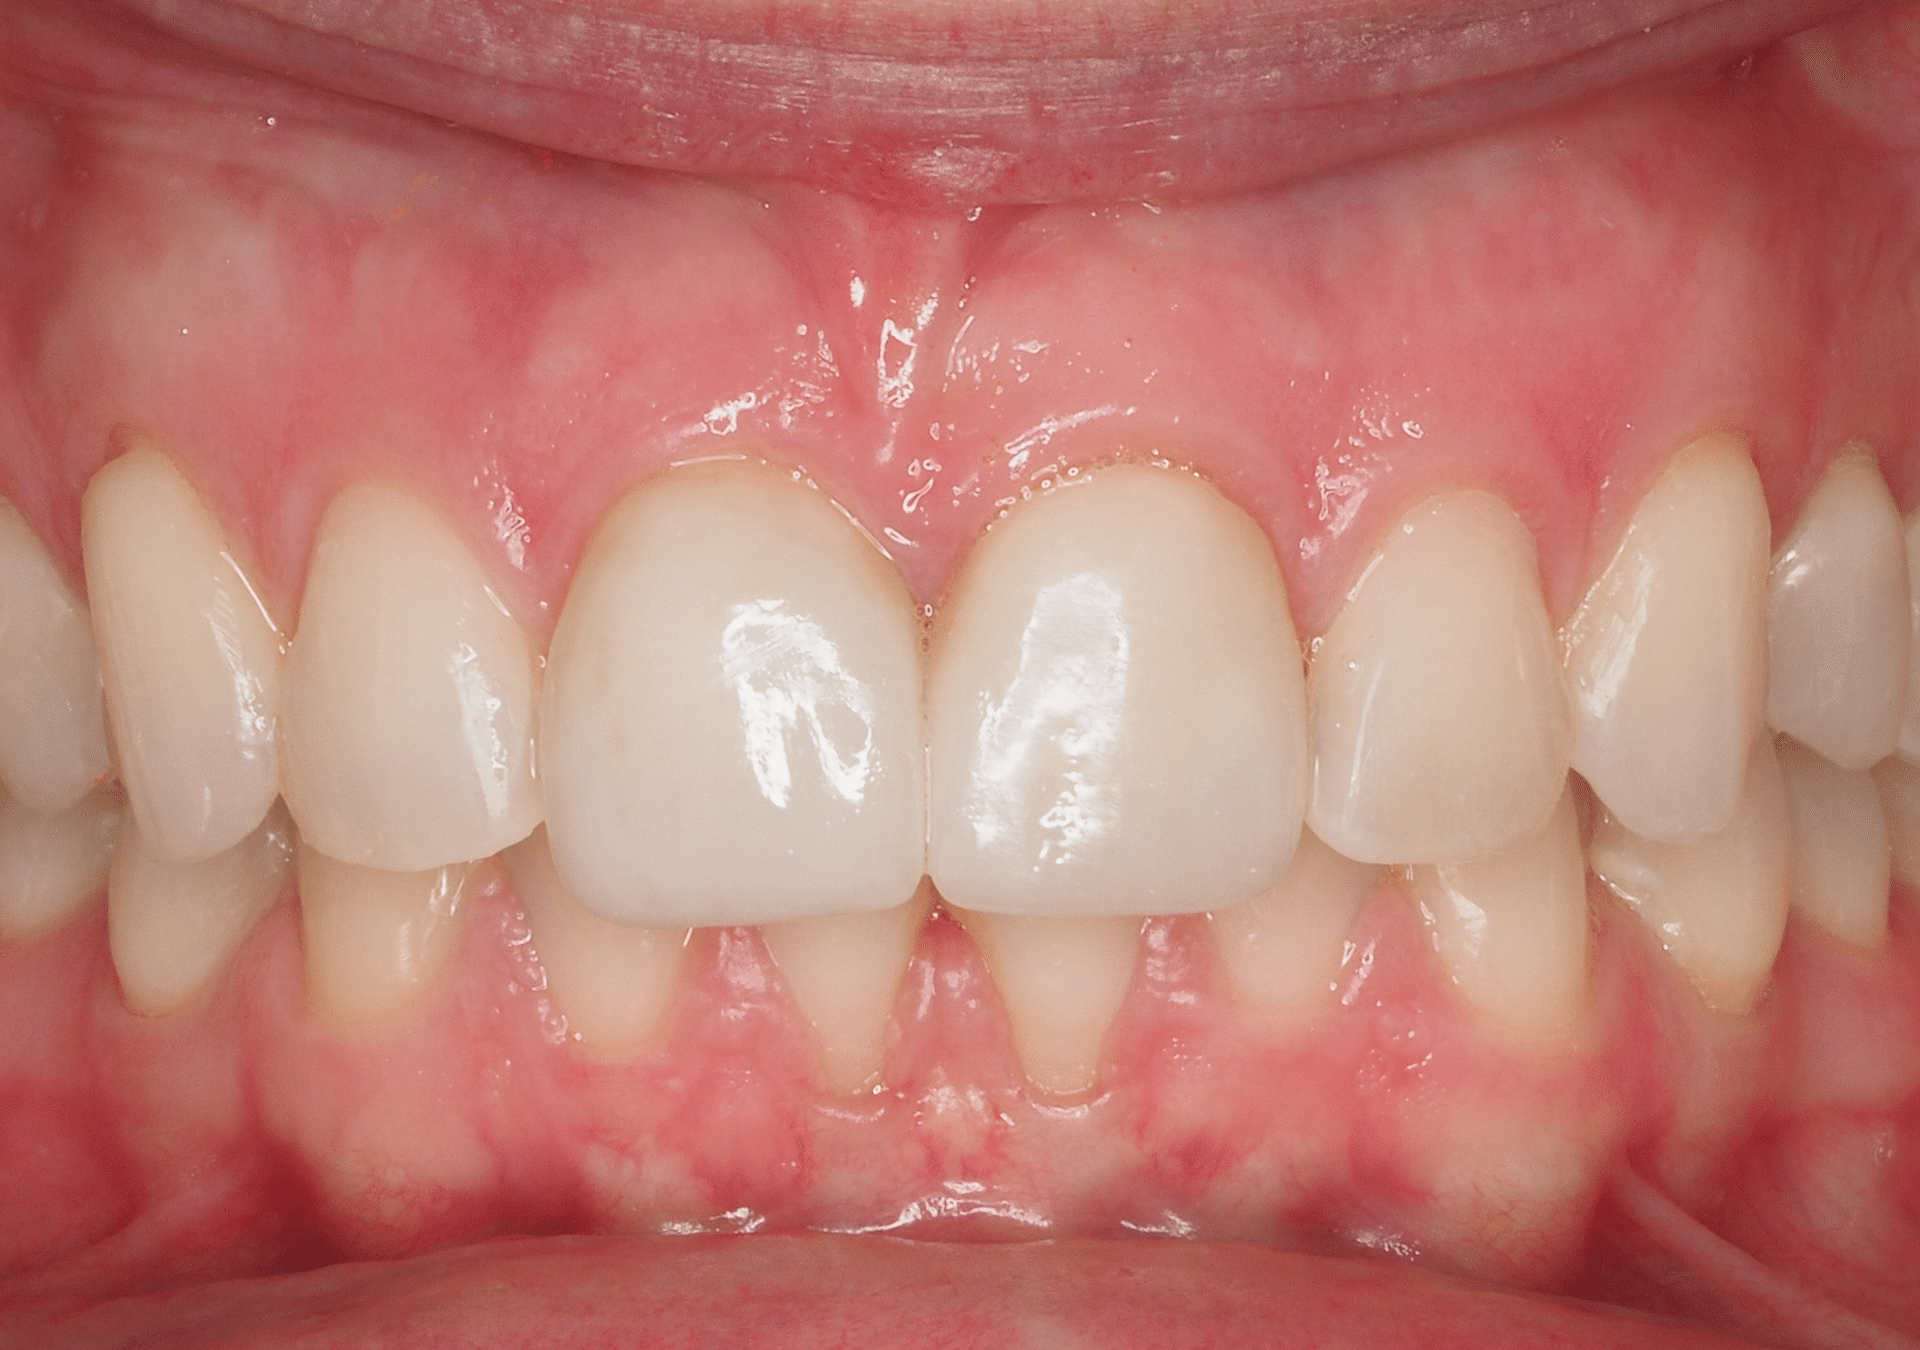

- 25 años de experiencia en restauraciones de resina de composite tanto en sectores anteriores como posteriores.

- Técnicas de aislamiento para garantizar la longevidad y la integridad de la restauración.

- Resultados estéticos comparables a la cerámica, de larga durabilidad.